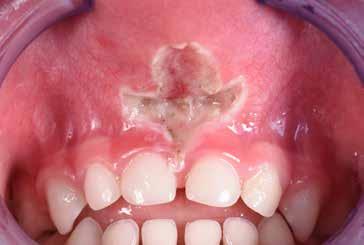

S.V. Paziente di tre anni di sesso maschile, in III Classe scheletrica lieve, con open-bite, deglutizione atipica, contrazione dell’arcata superiore, tendenza alla III Classe. Alla prima visita il paziente presentava un evidente frenulo vestibolare corto, a tetto labiale che, trazionando il labbro superiore, tendeva a ischemizzarsi insieme alla papilla retroincisiva.

In situazioni simili si potrebbe anche attendere ma, poiché si rendeva necessaria una terapia ortodontica, si è proceduto ad eseguire una frenulectomia e il giorno stesso è stato consegnato al paziente l’apparecchio elastodontico per la correzione della malocclusione. Lo scudo vestibolare dell’apparecchio ha contribuito alla guarigione del frenulo stesso determinando una trazione continua sul labbro superiore.

La sequenza terapeutica ha previsto i seguenti step:

• frenulectomia laser;

• terapia elastodontica al fine di ripristinare la corretta crescita scheletrica e dentale.

Fig. 4

Fig. 5 > Immagine intraorale frontale.

Fig. 6 > Immagine intraorale laterale destra.

Fig. 7 > Immagine intraorale laterale sinistra.

Fig. 8 > Dettaglio del frenulo labiale superiore corto.

Figg. 9-11 > Intervento di frenulectomia con laser a diodo.

Figg. 12, 13 > Controllo dopo ventiquattro ore.